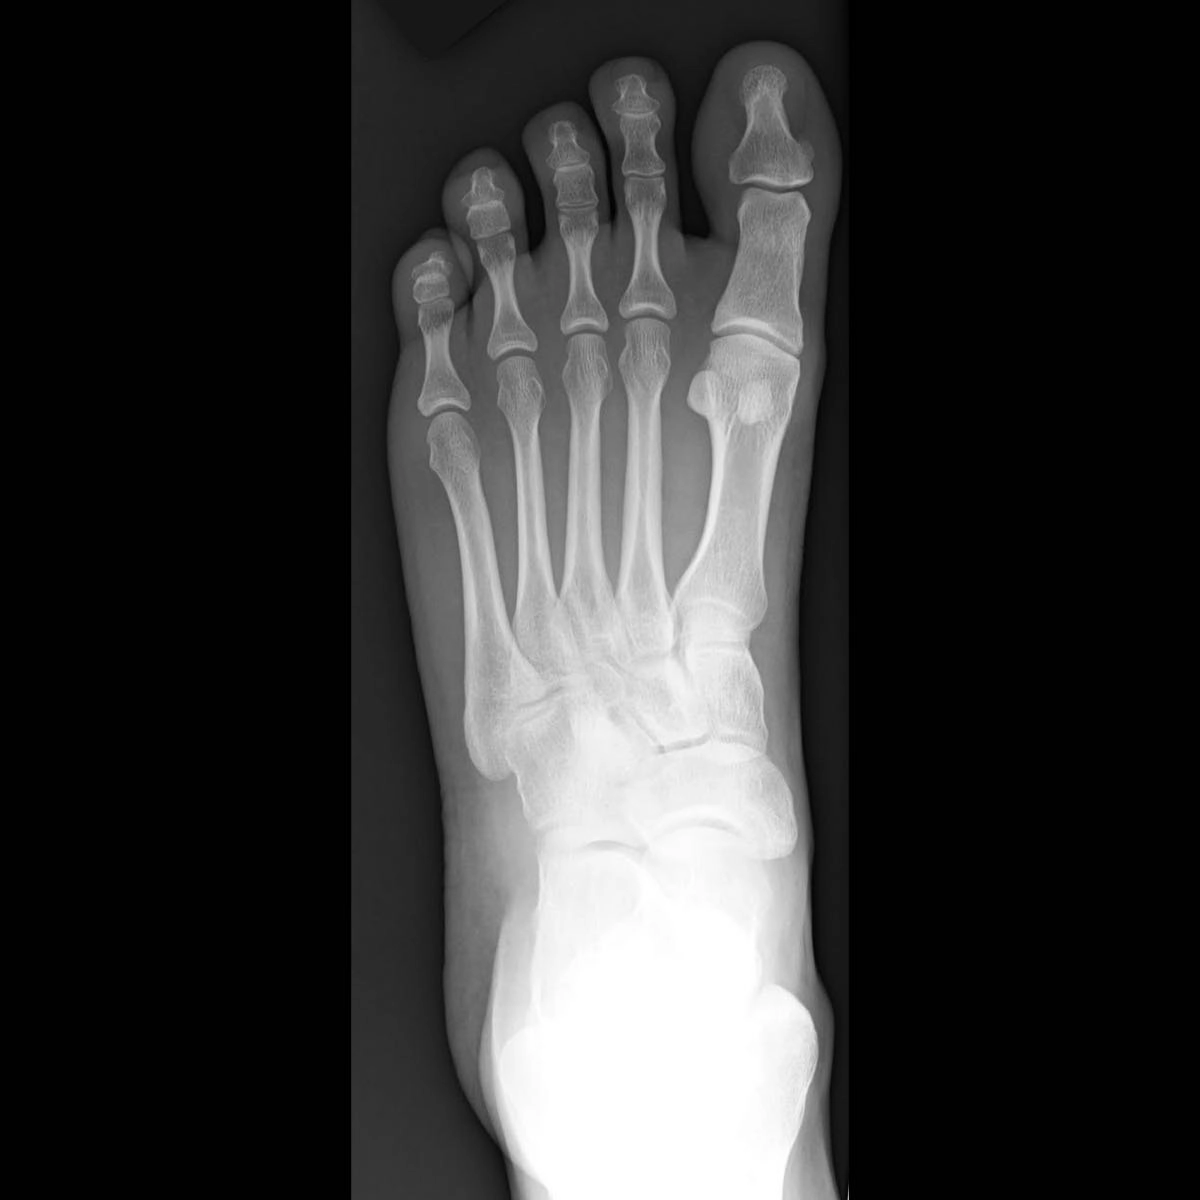

X quang bàn chân

16/03/2026